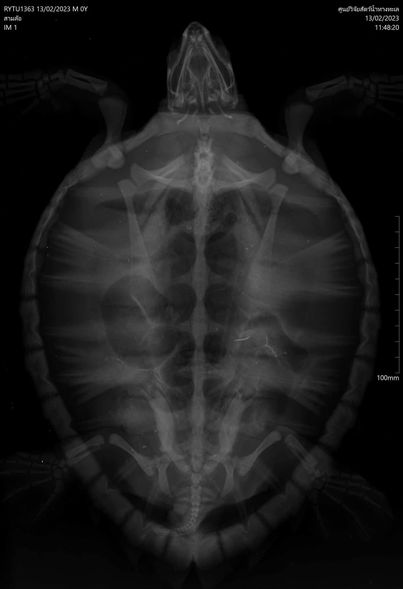

From checking it was found to be an Eretmochelys imbricata turtle, 32 cm long, 26 cm wide, and 2.45 kg weighing, a juvenile with no microchip number was found from a thorough physical examination found that the turtle also responsive with pale mucous membranes gas in the gastrointestinal tract was found during radiological examination and have more water in the body cavity than usual hematology test results anemia found low proteinuria and liver disease, however, the turtle received initial treatment and then will recover the body, when it returns to normal, it will be released back to nature.